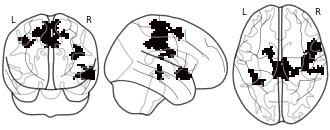

"description": "Multi-modal analysis in BPD. Brain regions exhibiting greater gray matter and enhanced activation during emotion processing in BPD compared to healthy controls. Note: Results were thresholded at p<.0025. Note2: Results were updated (see Erratum for this publication).",

"description": "Multi-modal analysis in BPD. Brain regions exhibiting smaller gray matter and enhanced activation during emotion processing in BPD compared to healthy controls. Note: Results were thresholded at p<.0025. Note2: Results were updated (see Erratum for this publication).",